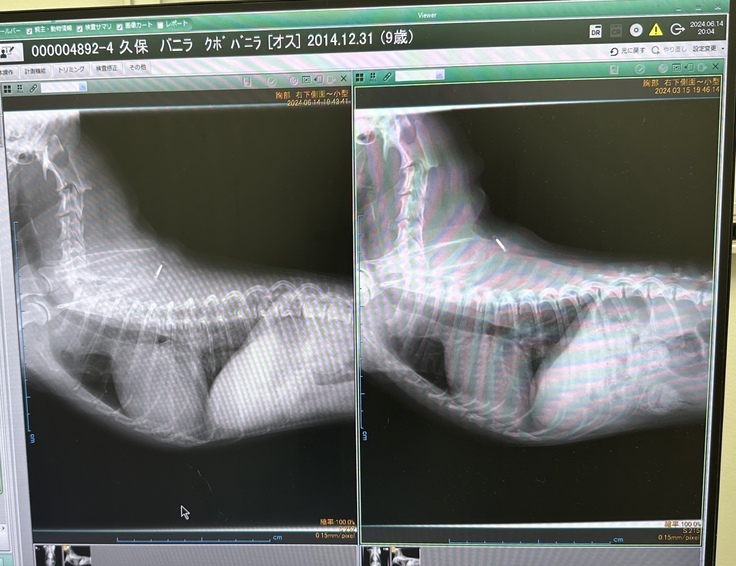

酸素室に少し入り、レントゲン・エコーの検査をしていただきました。

結果は、初期の肺水腫でした💦

心臓がやはり大きくなってきているので、

左が本日のX線。前より肥大してます。